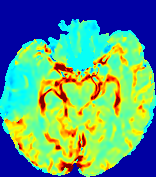

LesionRefer to captionRefer to captionRefer to captionRefer to captionRefer to captionRefer to caption𝐕rgbsubscript𝐕𝑟𝑔𝑏{\bf{V}}_{rgb}Refer to captionRefer to captionRefer to captionRefer to captionRefer to captionRefer to caption𝐕2subscriptnorm𝐕2{\|\bf{V}}\|_{2}Refer to captionRefer to captionRefer to captionRefer to captionRefer to captionRefer to captionRefer to caption3.53.53.52.82.82.82.12.12.11.41.41.40.70.70.70.00.00.0(mm/s)𝑚𝑚𝑠(mm/s)D𝐷DRefer to captionRefer to captionRefer to captionRefer to captionRefer to captionRefer to captionRefer to caption0.0200.0200.0200.0160.0160.0160.0120.0120.0120.0080.0080.0080.0040.0040.0040.0000.0000.000(mm2/s)𝑚superscript𝑚2𝑠(mm^{2}/s)Slice #1Slice #2Slice #3Slice #4Slice #5Slice #6

Figure 3: PIANO feature maps for one stroke patient, where the lesion is located in the left hemisphere. Top row: segmented stroke lesion region (white) on different slices, obtained from ISLES 2017. The corresponding slices for the PIANO feature maps are shown in the following rows.

For a better insight into an estimated velocity field 𝐕𝐕{\bf{V}} and diffusion field 𝐃𝐃{\bf{D}}, we compute the following maps: (1) 𝐕rgbsubscript𝐕𝑟𝑔𝑏{\bf{V}}_{rgb}: Color-coded orientation map of 𝐕=(Vx,Vy,Vz)T𝐕superscriptsuperscript𝑉𝑥superscript𝑉𝑦superscript𝑉𝑧𝑇{\bf{V}}=(V^{x},V^{y},V^{z})^{T}, obtained by normalizing 𝐕𝐕{\bf{V}} to unit length and mapping its 3 components to red, green, blue respectively; (2) 𝐕2subscriptnorm𝐕2\|{\bf{V}}\|_{2}: 222 norm of 𝐕𝐕{\bf{V}}; (3) D𝐷D: scalar field in Eq. 5.

Fig. 3 and Fig. 4 show the PIANO feature maps estimated from two ISLES 2017 patients: all are highly consistent with the lesion in both cases. Details of the blood flow trajectories are revealed in 𝐕rgbsubscript𝐕𝑟𝑔𝑏{\bf{V}}_{rgb} by the ridged patterns and the sharp changes of colors in the unaffected (right) hemisphere, while the flat patterns appearing within the lesion provide little directional information about the velocity and indicate low velocity magnitudes. Velocity magnitudes are more directly visualized via 𝐕2subscriptnorm𝐕2\|{\bf{V}}\|_{2}, from which one can easily locate the lesion where 𝐕2subscriptnorm𝐕2\|{\bf{V}}\|_{2} is low. D𝐷D also indicates lower diffusion values in the lesion, though with less contrast potentially due to the fact that it captures the accumulated effect of CA diffusion at the voxel-level.